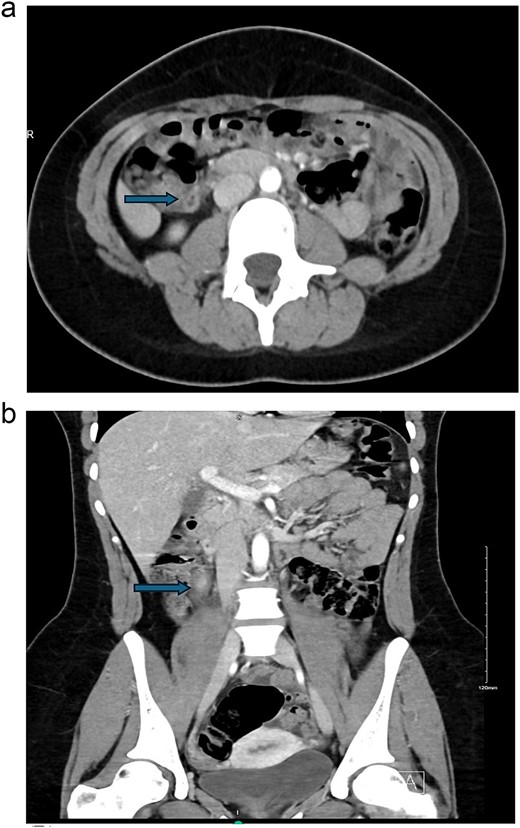

We are presenting a 19-year-old, single female patient, medically and surgically free, who presented to Emergency Department with a history of persistent right lower quadrant (RLQ) abdominal pain for 2 days, not improving and increasing in severity, no fever, and no previous similar attacks. On exam, she was stable, no tachycardia, no documented fever, and vital signs upon presentation: blood pressure 116/52 mmHg, heart rate 66 beats per minute, respiratory rate 20 frequency/min, saturating well 100% on room air. The abdomen exam was positive for RLQ tenderness, no rebound, negative Rovsing’s sign, no peritoneal signs. Labs were remarkable for white blood cells: 11.2 × 109/L and neutrophil shift: 8.92 × 109/L, other labs were within normal ranges; pregnancy and urinalysis were negative. Alvarado score was 7. Abdomen computed tomography (CT) scan done (Fig. 1) showed a dilated appendix up to 1 cm with mural edema and hyperenhancement surrounded by mild fat stranding, subcentimeter reactive lymph nodes, minimal free fluid, and thickened adjacent peritoneal reflection. There is no adjacent drainable collection. The unprepared small and large bowel loops are unremarkable. Impression was acute, uncomplicated appendicitis. Patient admitted, prepared for surgery, and laparoscopic appendectomy was planned on the same day of the admission. Intra-operatively, the cecum was identified, which was in the subhepatic area; we followed the taeniae coli; and the appendix was identified in the retrocecal area, and it had two bases, both of which were forming a horseshoe appearance, which is an anomaly of the appendix (Fig. 2). We dissected it off completely till the cecum. Decision made for stapling both bases with an endo-GIA 45 purple. Both bases were stapled. Clean bases were identified, and staple lines were clean, no bleeding, and it was completely healthy. Hemostasis was secured. The patient tolerated the procedure well. The patient was assessed the following day and was doing fine, tolerating orally, passing flatus, with an unremarkable abdominal exam. She was discharged the next day in stable condition. The patient was seen after 2 weeks from the discharge in the clinic and was doing well; clips were removed, and pathology confirmed the diagnosis of acute appendicitis with periappendicitis with a shape anomaly of the horseshoe appendix. Patient planned for colonoscopy in the outpatient department. Interval colonoscopy done that was unremarkable. Patient discharged from the clinic.

(a) Axial view and (b) coronal view showed a dilated appendix up to 1 cm with mural edema and hyperenhancement surrounded by mild fat stranding, subcentimeter reactive lymph nodes, minimal free fluid, and thickened adjacent peritoneal reflection.